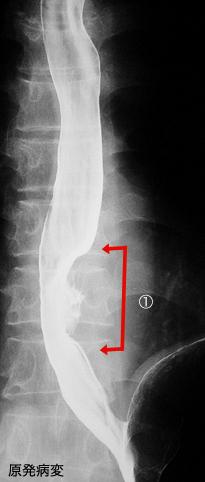

Criteria of Hist.ClassificationMalignant epithelial tumor/Squamous cell carcinoma

LocationEsophagus/Lower third

Technique, MethodX-ray

Macroscopic TypesType 3 Ulcerated type with infiltration/

Size35 - 40

Depth of Tumor Invasionserosa (adventitia)